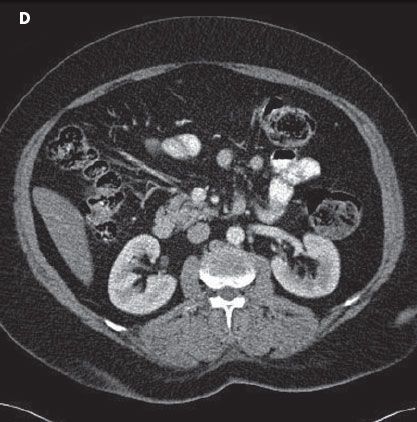

At our advice, the patient-who was taking 16 medications in total-discontinued aspirin therapy. Thereafter, the patient’s health improved and a diagnosis of NSAID-induced colitis was made. CT (D) and colonoscopy (E) done 6 months later showed complete resolution of the lesion. Our patient is currently controlling her arthritic joint pain with acetaminophen.

The pathogenesis of NSAID-induced colitis is controversial. Local and/or systemic effects of NSAIDs on mucosal cells might lead to an increased intestinal permeability, a prerequisite for colitis.4 NSAID-induced colitis is treated by discontinuation of the offending medication if possible and therapy with either sulfasalazine5 or metronidazole.6 Surgery is often indicated in cases of life-threatening complications or intractable symptoms.7